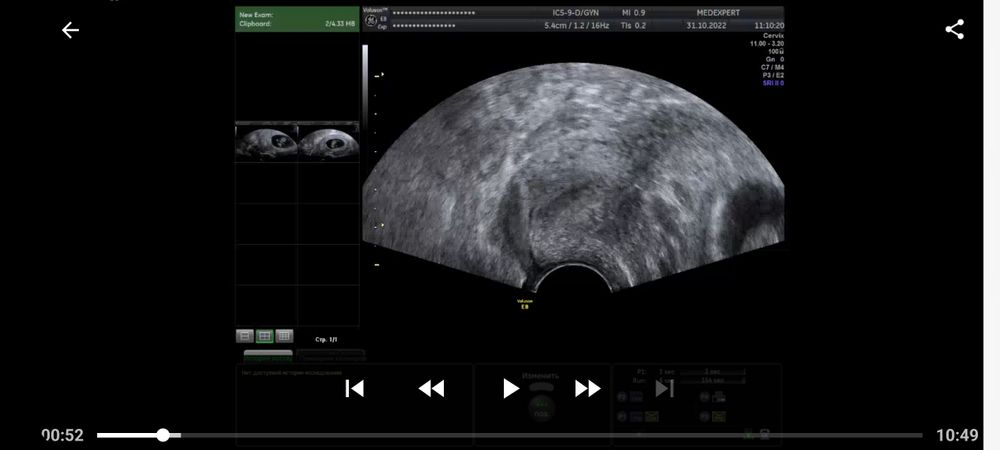

Ретрохальная гематома и мягкая шейка 9 недель беременности

9 недель и 3 дня срок. Сегодня сделала узи, по причине того, что в прошлый раз была отслойка 11×3мм (заключение прикладываю). В результате сегодня имеем прогрессирующую отслойку 27×3мм. Помимо этого шейка матки очень мягкая и губы свободно двигаются при перемещении датчика. Иногда тянет живот, не сильно, как перед месячными, только намного слабее. Выделения по цвету немного желтоватые, но не постоянно, а раз за несколько дней. А так, нормальные по цвету, без запаха. Кровяных или коричневых выделений нет. Прием у акушера-гинеколога только завтра. Приговор врача-узи заставляет нервничать и переживать, но пытаюсь отвлечься и успокоиться, была озвучена угроза прерывания беременности. Приехала домой и соблюдаю постельный режим до завтрашнего дня. Встаю только по крайней необходимости (туалет, покушать). Из препаратов ничего не принимаю, только витамины Элевит первый триместр. Как мне вообще вести себя в данной ситуации до приема врача? Чего бояться и при каких ситуациях вызывать скорую. Короче я напугана.